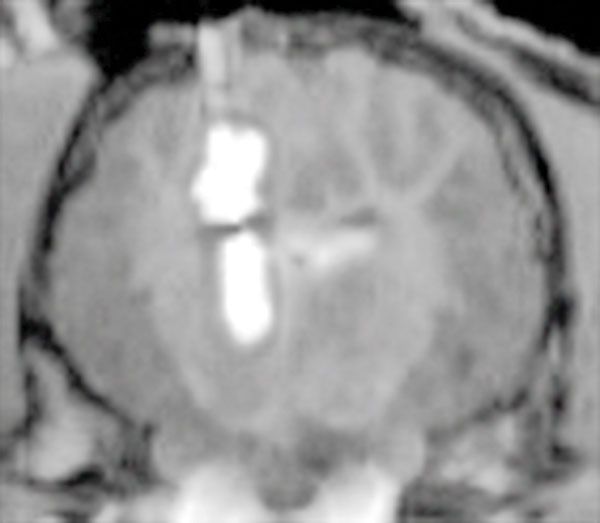

Figure 2 — OmniArray™ PBIC delivery of MRI contrast agent to porcine parenchymal brain tissue (high flow resistance) while also bridging the ventricle (low flow resistance).